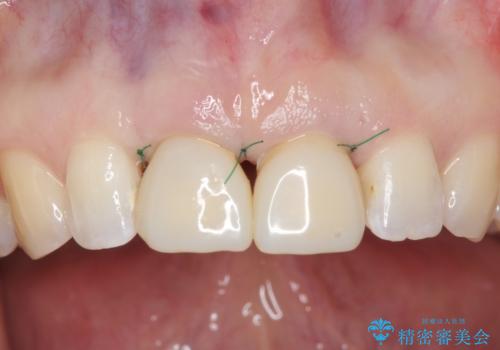

その後、マージンが舌側が深い状態だったため、歯ぐきの手術(歯周外科処置:APF)を行ってから最終的なセラミックを装着しました。

終了時